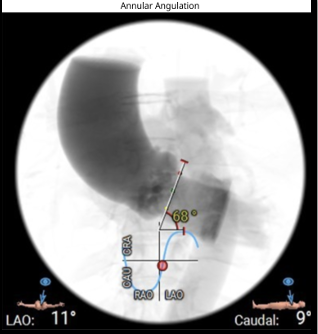

ECG revealed features of left ventricular hypertrophy. 2D echocardiography showed preserved left ventricular ejection fraction with severe calcific aortic stenosis, CT-TAVI protocol revealed Type 1 bicuspid aortic valve (R-L fusion), dilated ascending aorta, a perimeter-derived annulus of 22.2 mm (average 22 mm), sinus of Valsalva diameters RCC 29 mm, LCC 30.7 mm, NCC 32 mm, LVOT perimeter 22 mm, significant valve calcification, steep LVOT angle (68¡Æ), and well-sized, non-tortuous femoral access

The preprocedural risk assessment revealed a EuroSCORE II of 12.6% and an STS score of 16.1%, confirming prohibitive surgical risk. Advised for transfemoral TAVI, snare assisted delivery of self-expanding valve.